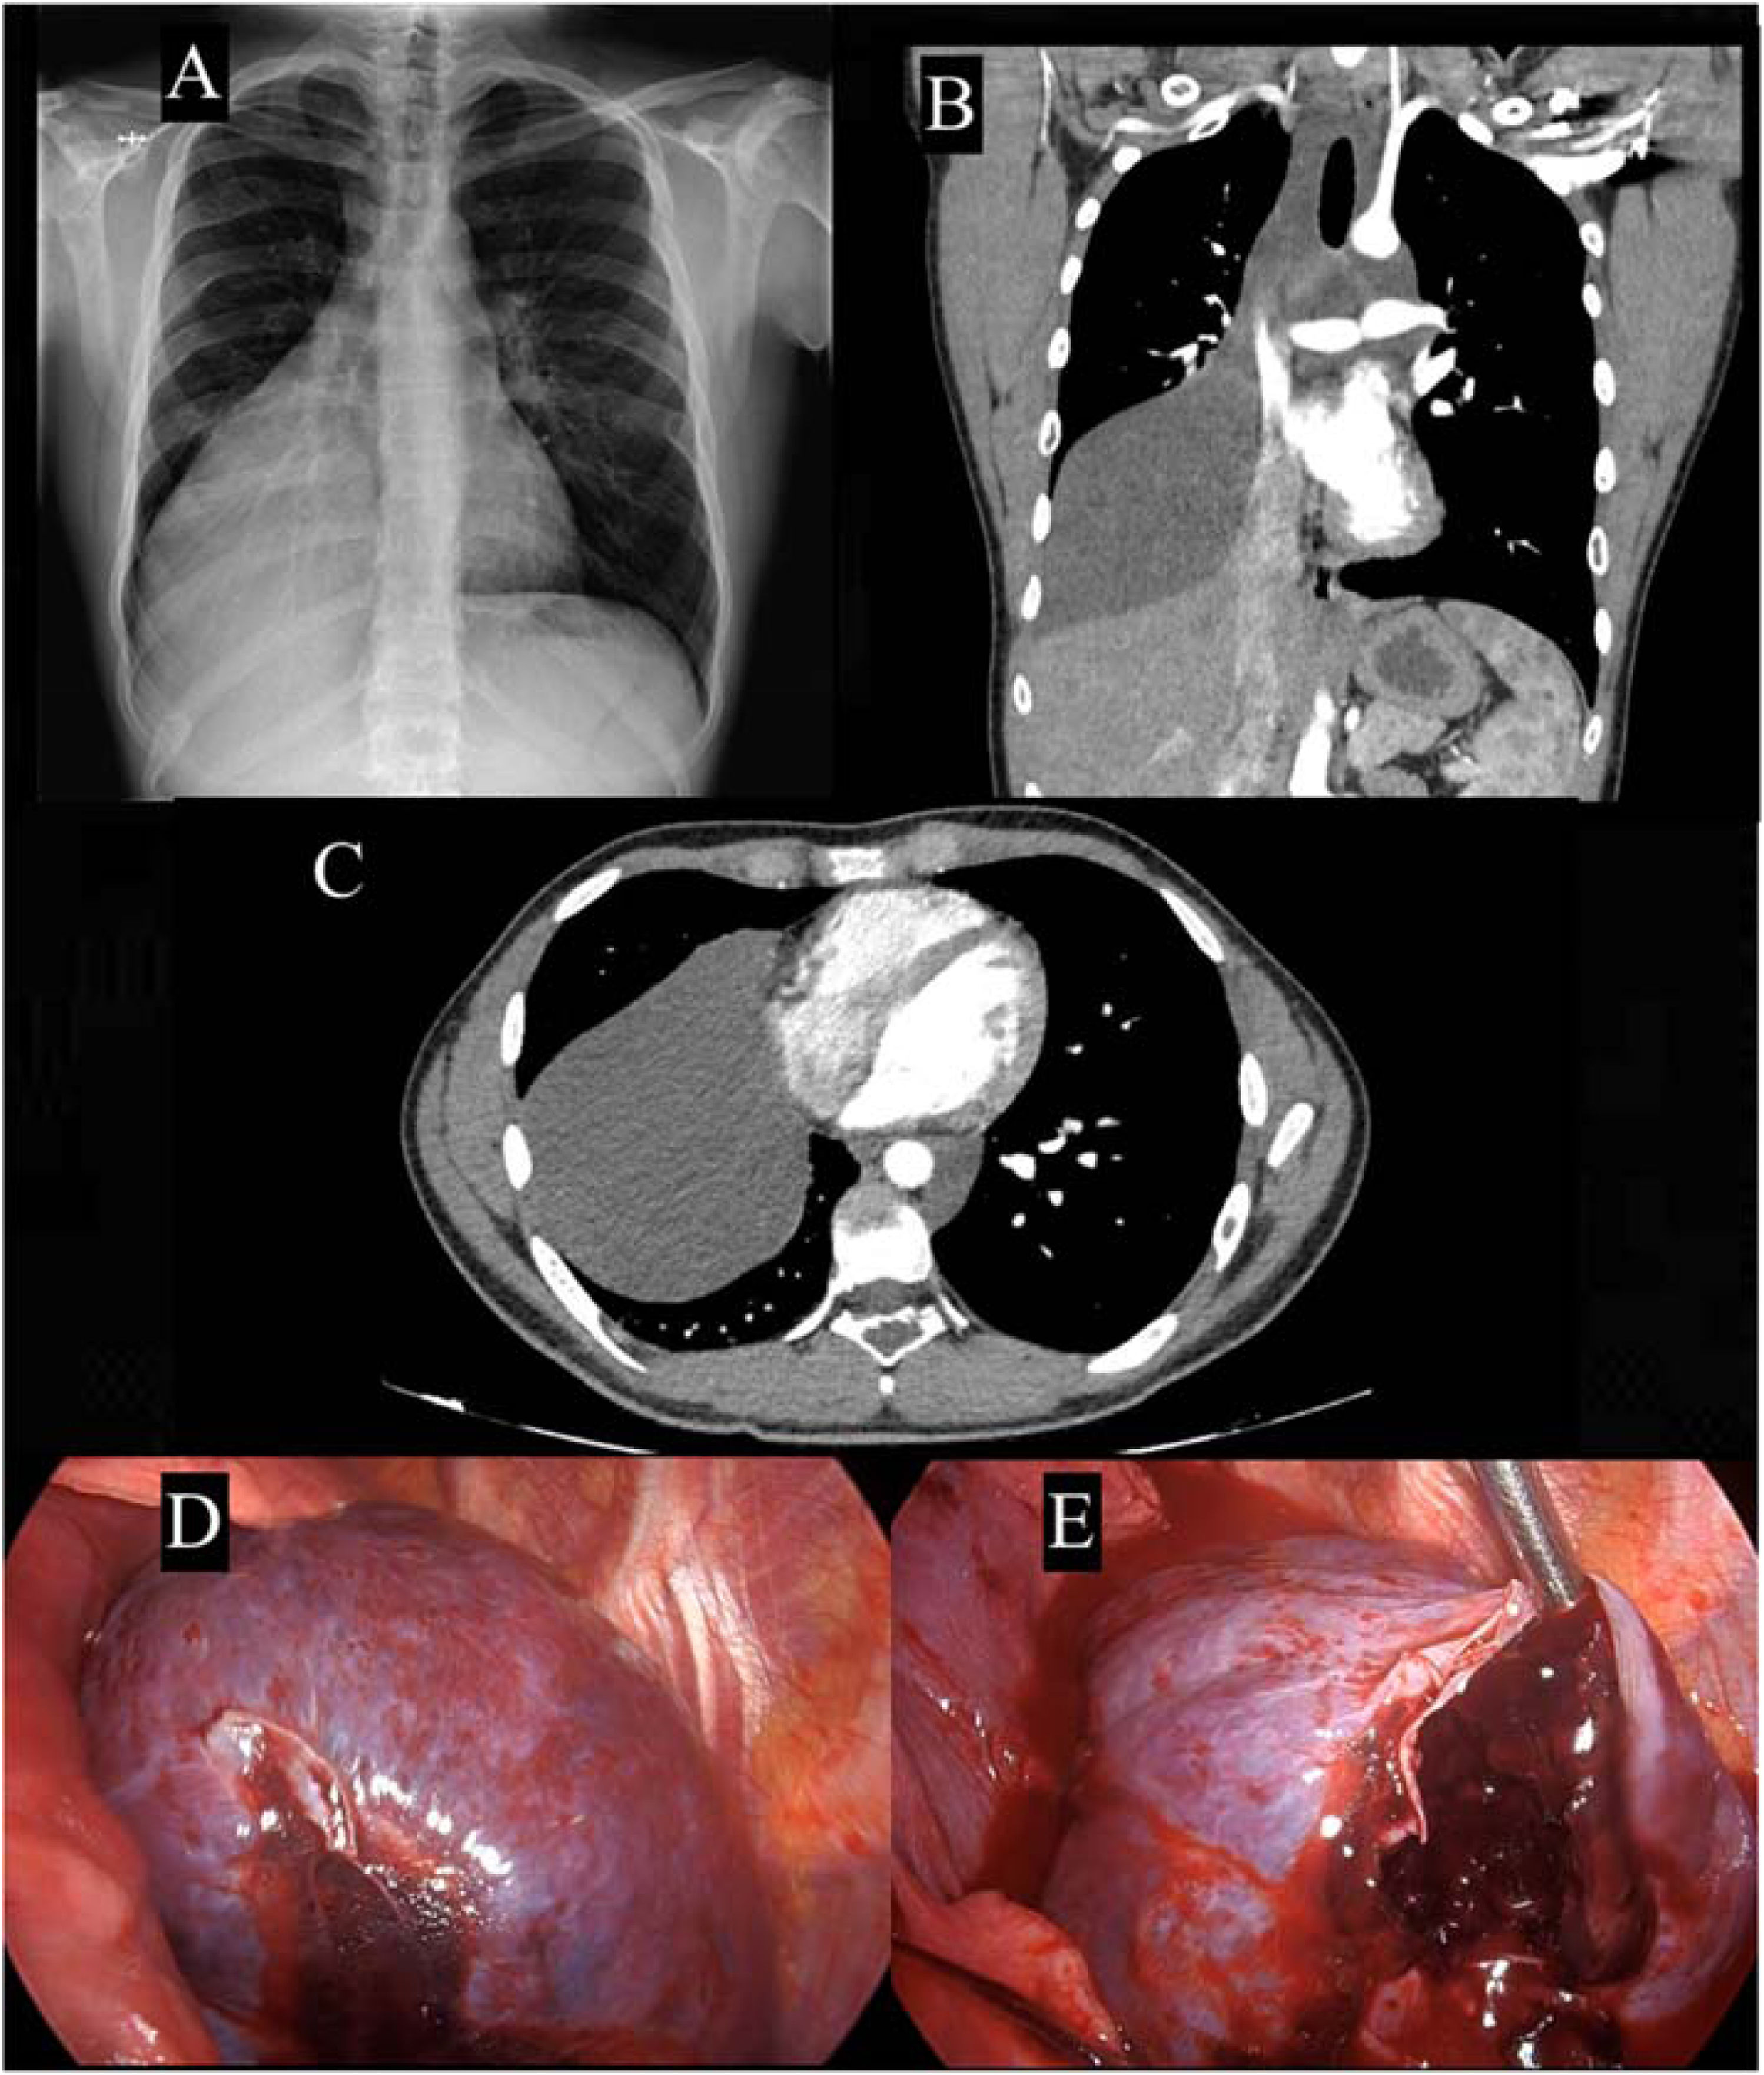

We present the case of a 19-year-old patient with history of recurrent non-chylous pleural effusions and a prior diagnosis of Gorham–Stout disease (GSD) based on a bone biopsy during childhood due to multiple osteolytic lesions. Admitted to the emergency department due to chest pain, a CT scan revealed a large pleuropericardial collection (Fig. 1A and B), for which he was referred to our centre. Surgery was indicated, with intraoperative findings of mediastinal lymphatic malformation with signs of complications, filled with blood and clots (Fig. 1C and D). Drainage and partial resection of the cystic lesion were performed, followed by analysis, leading to a diagnosis of cystic cavity lined by endothelial-type squamous epithelium without atypia, consistent with lymphangioma. Immunohistochemical staining showed positiveness for D2-40, CD34, and CD31, supporting a lymphatic nature. Gorham–Stout disease is a rare disorder characterized by osteolysis due to lymphangiomatous tissue progression. Typically manifests as osteolysis of the axial bone with pain as the most common symptom.[1] One of the known complications is the development of chylothorax.[2] Spontaneous internal bleeding from a cystic malformation is an extremely rare finding and life-threatening condition in a patient with Gorham–Stout disease.